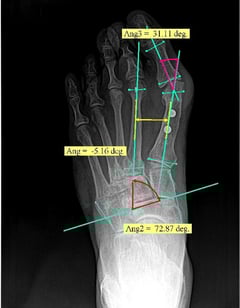

Metron-MD is human medical imaging software particularly focused on chiropractic and podiatry.

It features world class imaging algorithms, calibration and measurement tools, multi-image stitching, report generation, full DICOM compliance, and more.

Podiatry